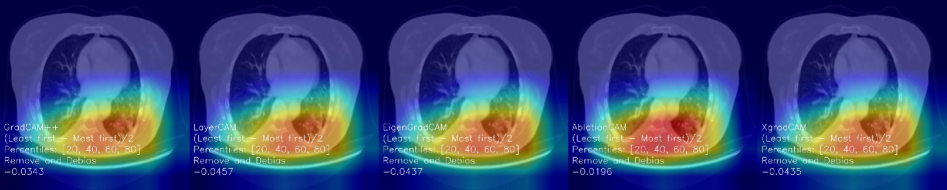

We selected ResNet34 as the network backbone, using skin cancer, brain tumor, chest cancer and multi-modality dataset, to investigate whether DA may improve the interpretability of the model while maintaining high classification accuracies. We use Gradcam++, LayerCAM, EigenGradCAM, AblationCAM and XgradCAM as the XAI methods. Furthermore, to provide a comprehensive evaluation as suggested in [3], we introduced a quantitative metric named remove and debias (ROAD) [17] to validate the DA model. The main idea of ROAD is to remove part of the image and then predict it again to measure the confidence change (higher is better).

Figure 7 illustrates the heatmap visualization obtained using five XAI methods and the confidence change (shown in the image as a number below the Remove and Debias symbols.) using ROAD for DA and without DA models on BT, SC and CC. We observe that: 1) for brain tumor images, the use of DA leads to better visual results as the model focuses more on the abnormal regions; In addition, the confidence change of DA model is higher compared to without DA (e.g., 0.0585 vs 0.0240 using GradCAM++). 2) for skin cancer images, the use of DA let the model focus more on the abnormal regions, while all XAI methods indicate higher overall confidence change. 3) for chest cancer, the potential of DA is limited, as it provides similar visual explanations and confidence changes compared to without DA (e.g., -0.0146 vs -0.0196). These findings suggest that DA can enhance diagnostic reliability for BT and SC by improving the focus of the model on abnormal regions and increasing confidence in predictions, but its limited impact on chest cancer highlights the need for domain-specific adaptations to ensure clinically significant improvements in all medical imaging tasks.